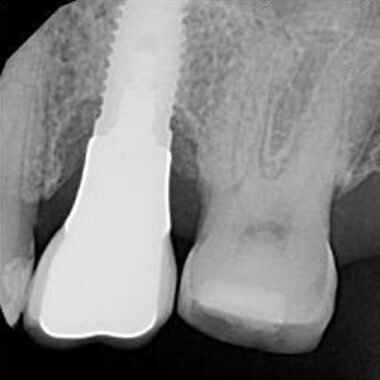

The patient was referred by Dr. K. for recovery of a fractured abutment screw in a 3i 5.0 implant in the #30 site. The fractured screw recovery protocol was reviewed with the patient and the top of the implant was conservatively cleared of excess tissue. The screw fragment was visualized to be below the first implant thread and was not easily mobile. A Type IV case in my treatment algorithm. A recovery system to mobilize the fragment was indicated. The fragment was spot drilled with a custom prototype drill and guide and adjusted until the spot was confirmed to be concentric on the screw fragment. Next, the fragment was drilled with a guided .8mm drill and fortunately the fragment was retrieved on the drill, which prevented a total drill out. The implant was cleaned, and the supplied healing abutment was placed finger tight. The patient was referred back to Dr. K. for continuation of his restorative care. The implant appeared intact and there is no indication that the prognosis for the implant will be altered secondary to the screw facture of the retrieval process.